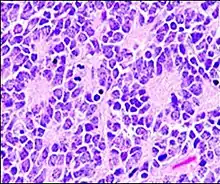

A pseudorosette is a perivascular radial arrangement of neoplastic cells around a small blood vessel. Pseudorosettes are present in neuroblastoma, medulloblastoma, malignant melanoma, ependymoma, Merkel cell carcinoma, neuroendocrine tumor of skin, seborrheic keratosis, dendritic cell neurofibroma, astroblastoma, large cell neuroendocrine tumor of cervix, clear cell ependymoma of spinal cord, celiac disease, nasal tumor of olfactory origin, rosette forming glioneural tumor (RGNT), oncocytoma, Wilm's tumor, pheochromocytoma of urinary bladder.[2]

Perivascular pseudorosette

A perivascular pseudorosette consists of a spoke-wheel arrangement of cells with tapered cellular processes radiates around a wall of a centrally placed vessel. The modifier “pseudo” differentiates this pattern from the Homer Wright and Flexner-Wintersteiner rosettes, perhaps because the central structure is not actually formed by the tumor itself, but instead represents a native, non-neoplastic element. Also, some early investigators argued about the definition of a central lumen, choosing “pseudo” to indicate that the hub was not a true lumen but contained structures. Nevertheless, this pattern remains extremely diagnostically useful and the modifier unnecessarily leads to confusion. Perivascular pseudorosettes are encountered in most ependymomas regardless of grade or variant. As such, they are significantly more sensitive for the diagnosis of ependymomas than true ependymal rosettes. Unfortunately, perivascular pseudorosettes are also less specific in that they are also encountered in medulloblastomas, PNETs, central neurocytomas, and less often in glioblastomas, and a rare pediatric tumor, monomorphous pilomyxoid astrocytomas.[2]

- Micrograph of perivascular pseudorosettes